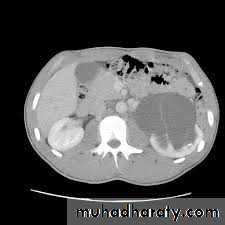

DIAGNOSIS

IVUDIAGNOSIS

CTTreatment